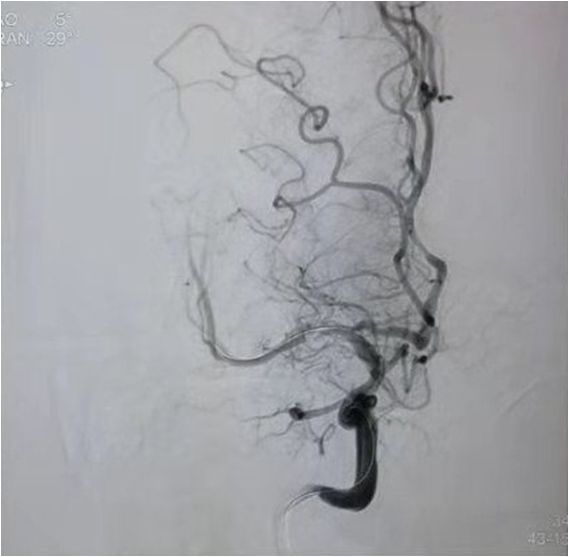

急诊MRA示:基底动脉尖丢失,决定急诊取栓再通。

双侧颈内动脉

双侧椎动脉

左侧椎动脉

分析该患者:目前神志清楚,双侧肌力4级,基底动脉前向血流3级,且患者取栓术后可能需要支架植入术,术后需要常规双重抗血小板聚集治疗,与患者丘脑出血治疗相矛盾,拟病情平稳后择期支架植入术,综合考虑后,结束造影,中性治疗。

一把拉通后,前向血流即刻恢复至3级,双侧小脑上动脉、大脑后动脉、基底动脉尖显影。

现基底动脉残余狭窄约40%,观察20min前向血流3级;斑块累及小脑前下动脉;右侧丘脑出血转化,尽可能避免双抗,综合考虑后放弃急诊支架植入,术后给予盐酸替罗非班泵入维持血流稳定。